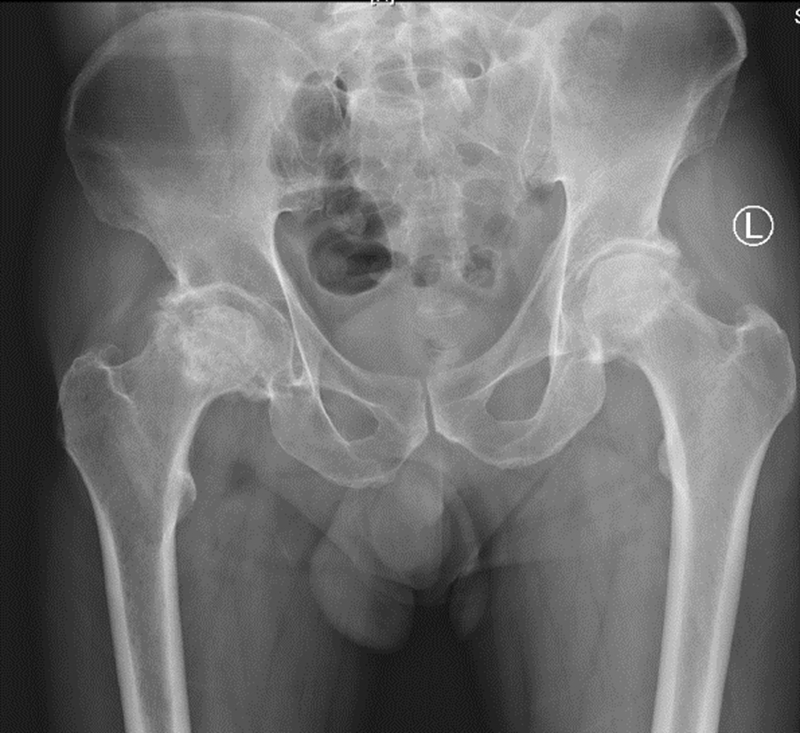

患者男性,48岁,诊断为“股骨头坏死”(图3),接受了VTS导航辅助下初次双侧全髋关节置换术,手术顺利,一侧手术仅用时约60分钟。术后影像学结果显示,假体位置、角度和肢体长度都非常满意(图4),次日患者即可下地活动,术后3日后即平稳出院。

图3 患者术前X光片,48岁男性,双侧股骨头坏死

图4 患者术后X光片,假体位置和角度理想,下肢偏心距和长度得到了重建